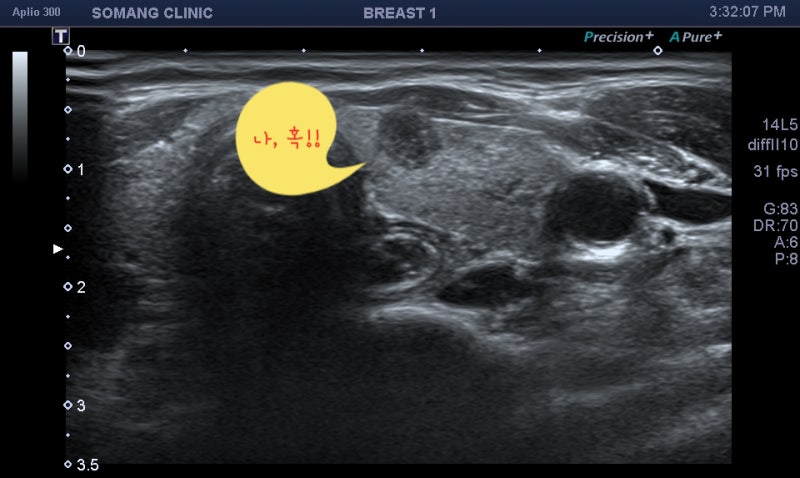

갑상선 석회화 결절의 진단은 갑상선 초음파로 결절의 위치, 개수, 모양, 크기, 내부, 비율, 경계 등을 자세히 관찰하는 것이다. 이로부터 이상이 발견되면 악성의 위험성을 예측할 수 있고 세침흡인세포검사를 시행할 수 있다. 동시에 정상적인 갑상선 기능을 확인하기 위해 혈액 검사를 실시합니다. 그러나 갑상선 초음파에서 갑상선에 석회화된 결절이 보인다고 해서 반드시 갑상선암으로 진행되는 것은 아닙니다. 첫째, 갑상선 결절의 크기가 5mm 이상인 경우 추가 생검이 필요합니다. 그러나 갑상선 석회화가 많이 진행된 경우에는 조직세포 채취에 어려움이 있을 수 있습니다.의정부갑상샘선 김수연유한의원

갑상선 초음파에서 발견된 모든 갑상선 결절이 외과적 제거가 필요한 것은 아닙니다. 갑상선암의 위험이 없는 양성결절이거나 크기가 불확실한 형태의 결절이라면 정기적인 건강관리와 함께 모니터링하면서 6개월 후 갑상선 초음파를 반복하면 진단이 가능하다. 의정부갑상샘한의원 김수연병원은 최고의 장비를 갖추고 있어 당일 검사 한번으로 빠르고 정확하게 진료가 가능합니다. 유방갑상선영상의학과 김수연 원장은 풍부한 경험을 바탕으로 정밀한 검사를 통해 갑상선 석회화 결절을 진단한다. 갑상선 결절이 의심되는 증상이 있으신 분들은 김수연 한의원에 내원하셔서 갑상선 검사를 받으시기 바랍니다.